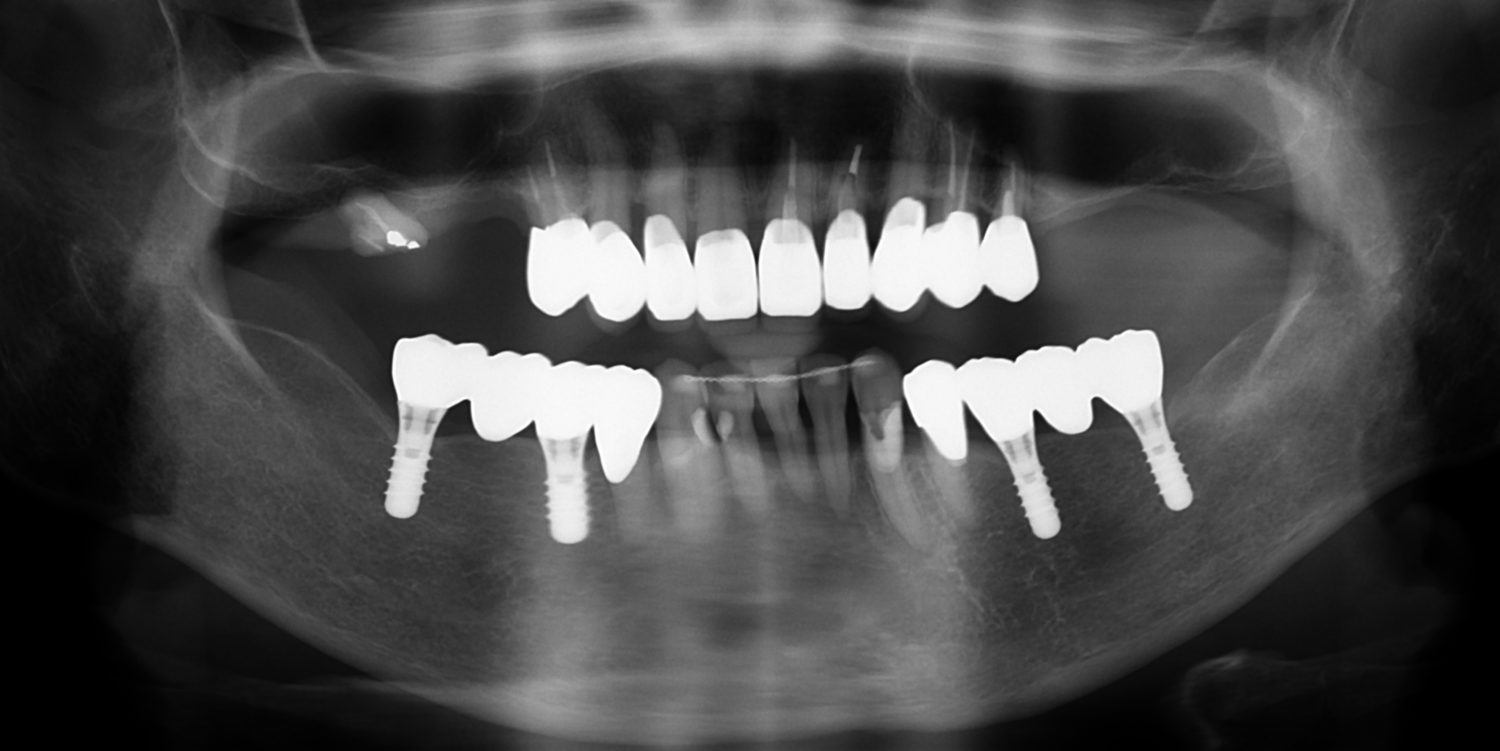

矯正治療・インプラント治療・セラミック治療・金属床(部分入れ歯)の症例紹介(三隅歯科クリニック)

三隅 賢祐(三隅歯科クリニック)

症例詳細

| 主訴 | 50代女性 以前いれた入れ歯が合わなくて使っていないので、しっかり噛めるようになりたい |

| 治療内容 | 矯正治療、インプラント治療、セラミック治療、金属床(部分入れ歯)を行いました。 |

| 治療費 | 4,200,000円(税込み) |

| 治療期間 | 2年(矯正治療期間 1年) |

| 治療回数 | 50回 |

| 想定されたリスク | 重度の歯周病で臼歯部の歯槽骨がかなり吸収していたため、インプラントが脱落するリスクがありました。 |